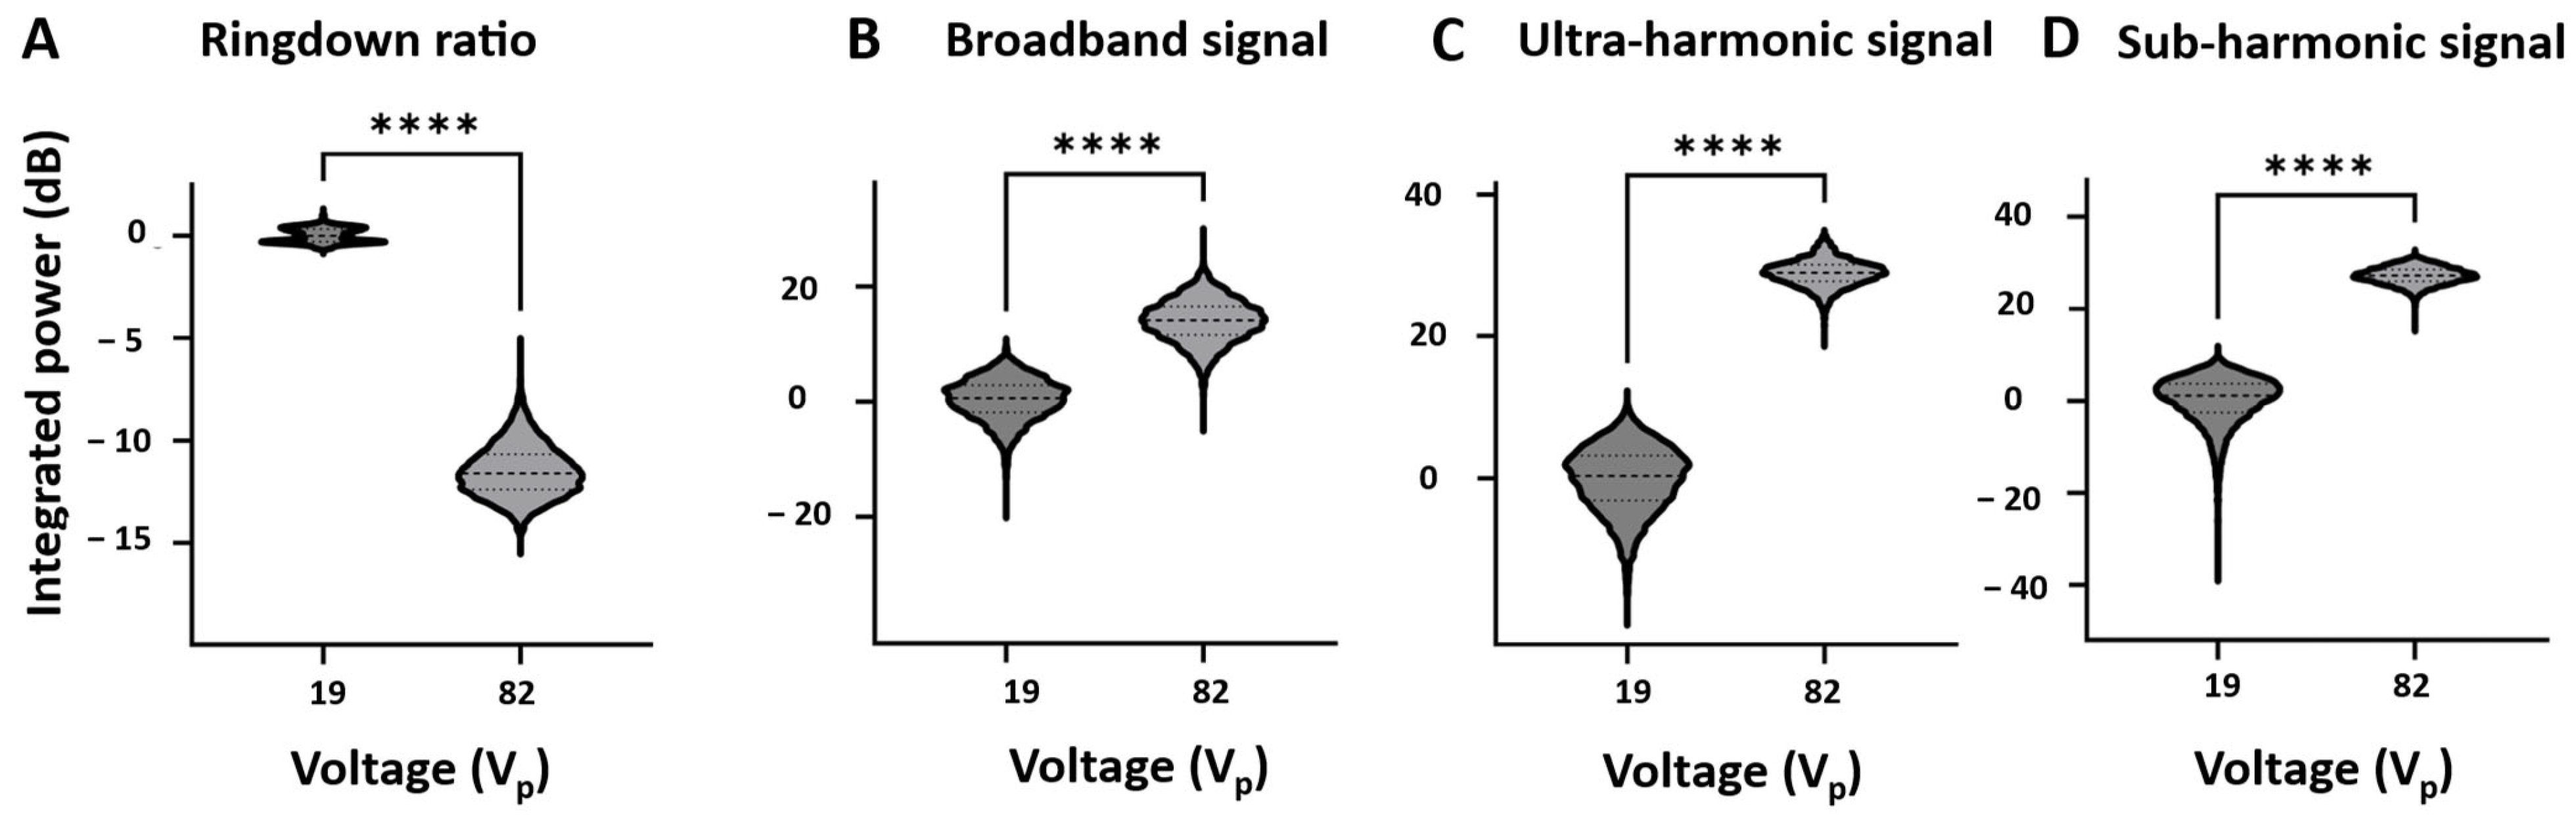

3.3. Self-Sensing Signals in Water-Filled Lumens

3.4. Self-Sensing Signals During Clot Treatments

4. Discussion